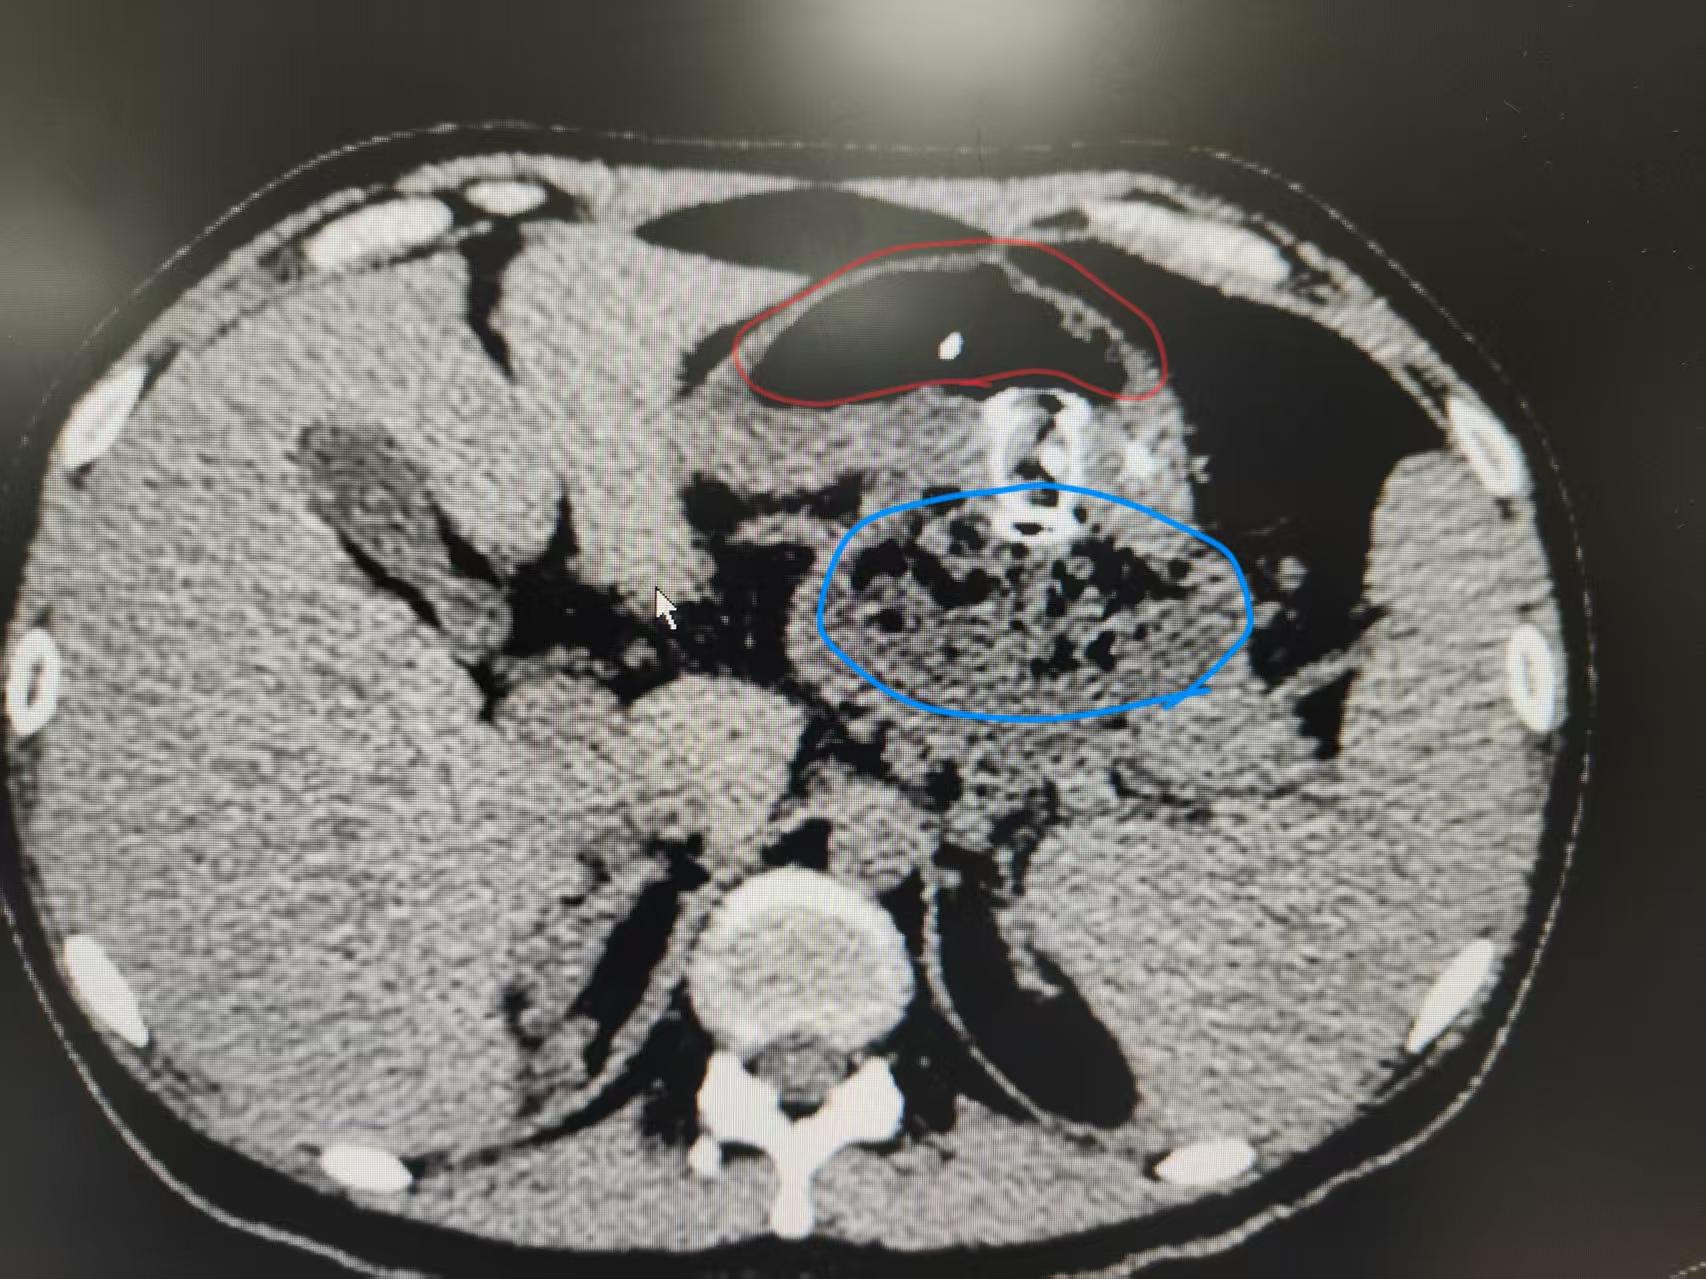

术后效果:立竿见影,快速康复

术后患者腹围迅速减小,腹胀、呕吐等症状快速缓解,逐渐恢复饮食,目前恢复良好。

术后CT(假性囊肿明显缩小,支架位置良好)